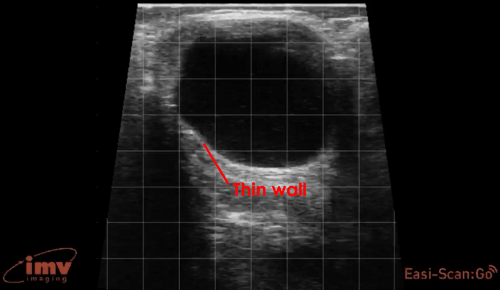

Ovarian Cysts

In this image, a large fluid-filled follicular cyst can be seen. Note the thin wall of the cyst.